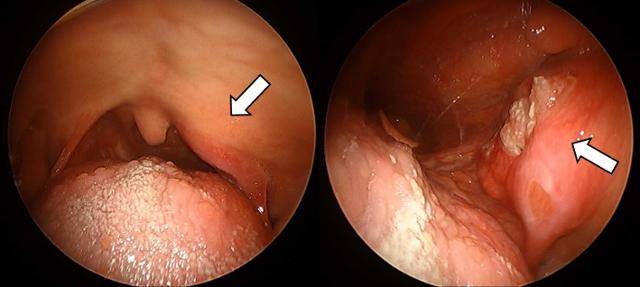

목과 편도가 붓고 구강 뒤쪽의 통증을 호소하며 병원을 찾는 환자들 중 구강암을 걱정하며 찾아오시는 분들이 있습니다. 대부분은 염증성이지만, 구인두암의 경우에는 신체 검진만으로 악성을 완전히 배제할 수 없는 경우가 많기 때문에 CT나 MRI와 같은 영상의학적인 검사 및 조직검사가 필요할 수 있습니다.

삼킬 때 어려움이 있거나 통증이 있을 경우, 목에 걸린 느낌이 지속되는 경우, 인후에 사라지지 않는 백색반 혹은 붉은 반점, 염증성 궤양이 2~3주 이상 지속되는 경우에는 이비인후과 내시경을 포함한 검진을 받아볼 것을 권합니다.

특히 림프절(임파선) 전이가 첫 증상으로 나타나는 경우가 많기 때문에, 통증을 동반하지는 않더라도 목에 혹이 만져지는 경우라면 반드시 전문가의 진찰을 받아보아야 합니다.